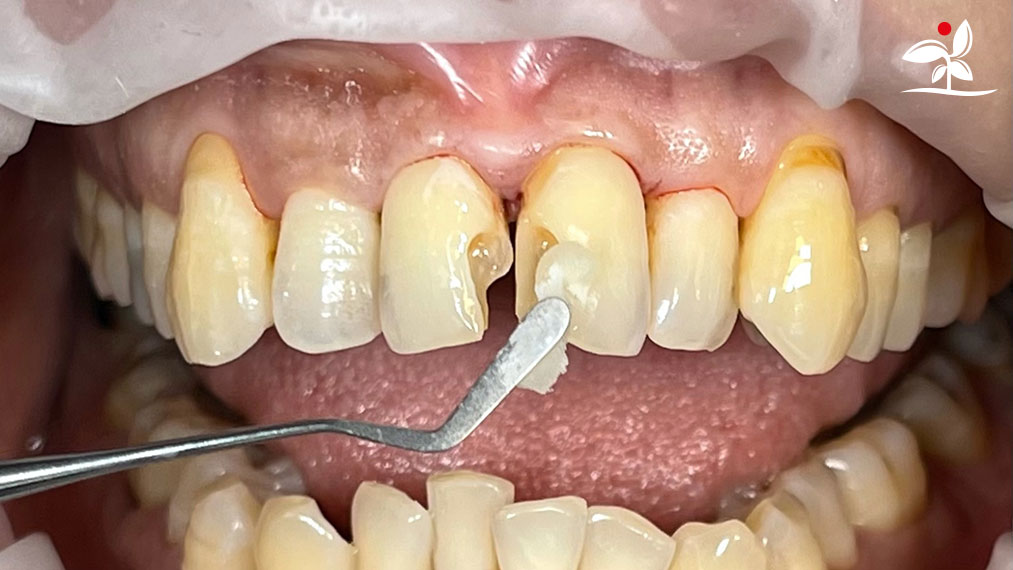

Restoration of Class IV Lesions using Naturomimetic Layering Technique (NLT) and Bioactive Restorative Materials

With the growing awareness about the health, function and aesthetic benefits of preserving natural tooth structure, patients are now globally demanding for aesthetic dentistry with minimally invasive procedures that has a low biological cost. This public demand has encouraged logical clinicians to adopt to the minimally invasive cosmetic dentistry (MiCD) concept and its treatment protocol [1] in their practice. The author has been using MiCD concept and its treatment protocols since 2017, which

include the methods of treatment that are simple, fast, predictable and healthy. In aesthetic restoration, the tooth color restorative materials placement technique is one of the most challenging, confusing and frustrating areas to learn owing to the multiple techniques that have been proposed by many clinicians and replicating such techniques in practice is not always as easy as they are marketed in dentistry. Natural teeth are complex in structure and hard to simulate due distribution of colors through enamel and dentin [2]. Aesthetic restoration strategies should follow proper understanding of defects, right selection of restorative materials along with their proper application, finishing, texturing and polishing [2].